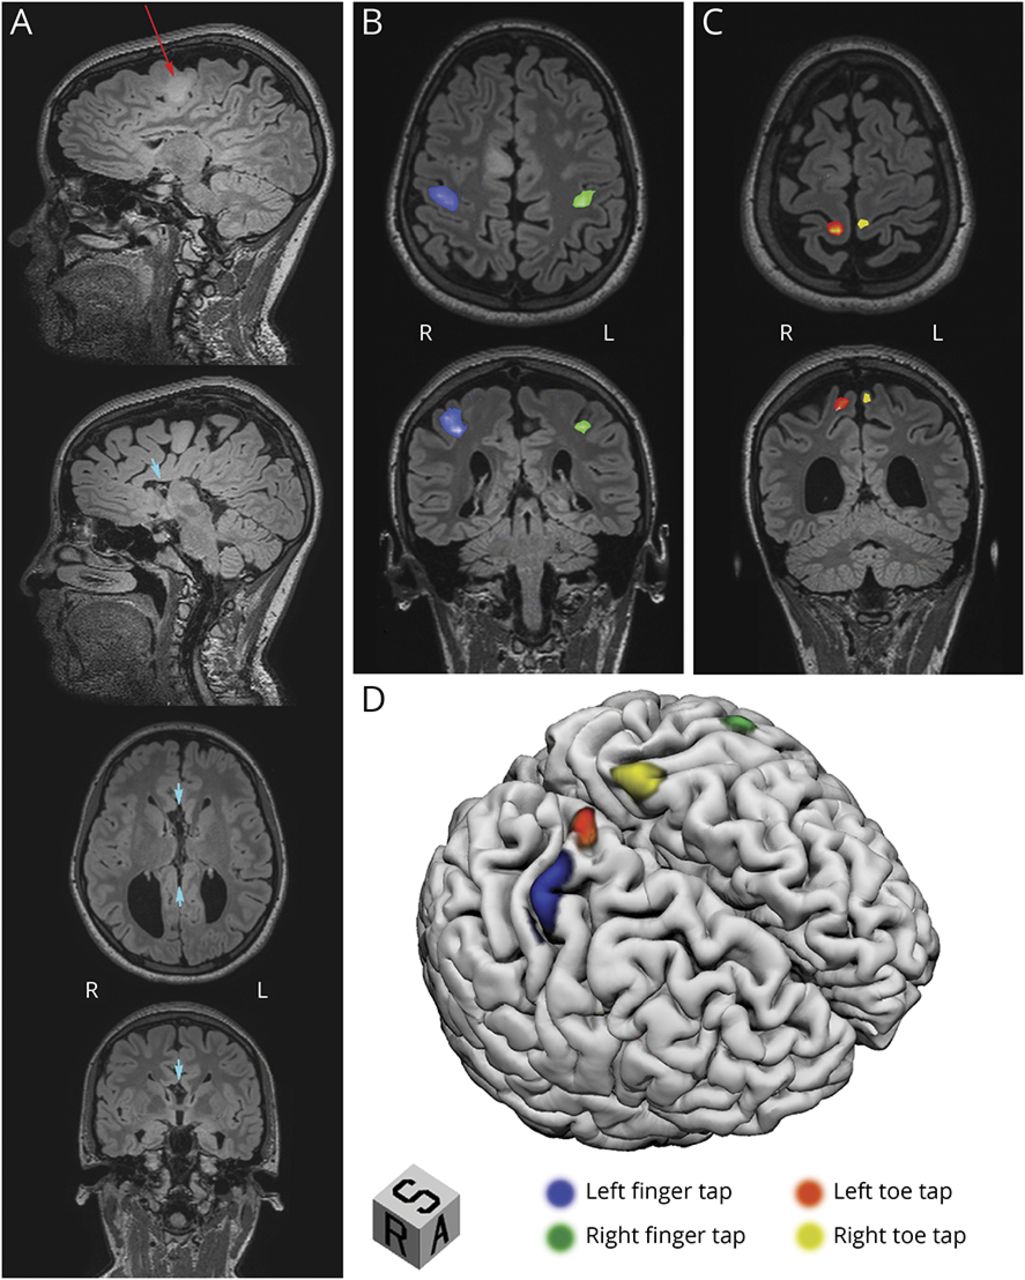

一个16岁的右撇子的女孩完成ACC是指耐火材料的7年历史的门诊头痛。最初的神经系统检查是正常的。大脑核磁共振确认完整的ACC和显示nonenhancing病变局限在对SMA暗示的低级神经胶质瘤(LGG) (图1一个)。执行基于任务的功能磁共振成像(eMethods中描述方法的补充,links.lww.com/WNL/C57)和显示手指和脚趾的位置点击激活将区域内的侧感觉运动皮层,但没有SMA活动(图1 b和C)。语言任务披露包括扩散双边演讲表示双方SMA。考虑到缺乏CC纤维和假定降低术后功能补偿的可能性,永久的风险赤字切除后SMA被认为是可观的。然而,因为穷人的结果常与LGG,姑息性手术治疗是有利的。SMA的皮质stimulation-guided总计切除肿瘤。

(一个上项)矢状天赋的T2加权MRI序列显示2.5厘米hyperintense渗透性的肿瘤局限在正确的辅助运动区(SMA;红色箭头)。(低,3项)矢状轴和日冕天赋的T2加权MRI序列强调没有胼胝体(CC;短青色箭)。(B和C)轴向和冠状fMRI显示blood-oxygen-level-dependent(粗体)激活的中间部分侧初级感觉运动皮层在手指敲(B)和上级的方面对侧初级运动皮层在脚趾(C)。(D) T1地基三维重建与叠加区域激活运动任务显示在解剖学上整合功能区域。